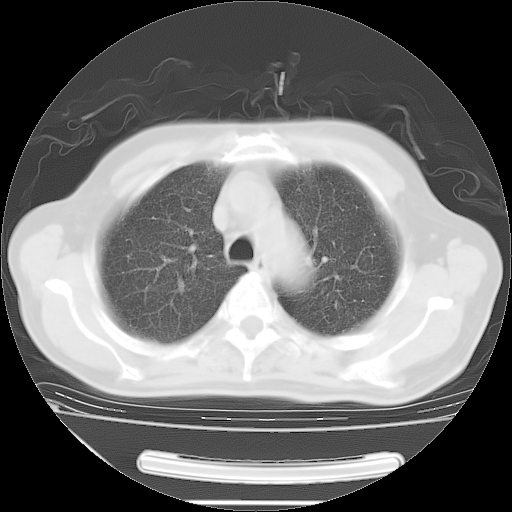

今天复查肺部CT,发现双肺广泛磨玻璃样改变。所以我把3月19日和5月9日相隔50天的肺部CT上传。请大家会诊。

2009年3月19日肺部CT片。

5月9日肺部CT(在4月27日齐鲁医院肺部CT描述部分肺组织磨玻璃样改变,12天后肺组织广泛磨玻璃样改变)

大致读了系列胸部CT:纵隔窗无明显异常,肺窗:从4、27至今:主要是双肺中下野外带可见毛玻璃样改变,目前处于急性肺泡炎阶段,至于原因考虑1、结替组织或胶原血管性疾病所致?2、恶性疾病如恶组在肺部所致的表现或细支气管肺泡癌?3、药物或其它原因如肺蛋白沉着症所致肺泡炎目前不太可能?总之,明天就去请我院的呼吸科、感染科、血液科和临免专家会诊哈。